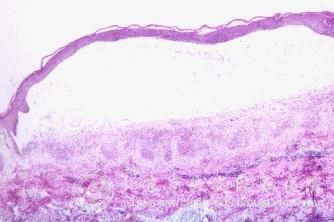

变态反应性过敏性接触皮炎的特点有什么?北京京城皮肤医院指出,过敏性接触皮炎是常见的皮肤病类型中的一种,常常由于各种原因引起过敏性接触皮炎,过敏性接触皮炎皮肤症状表现复杂,而且过敏性接触皮炎发展迅速。北京京城皮肤医院就给大家讲解变态反应性过敏性接触皮炎的特点。帮助大家及早的发现过敏性接触皮炎,预防过敏性接触皮炎的发生。

北京京城皮肤医院指出,变态反应性过敏性接触皮炎:由于此型皮炎的接触物质往往不具有强烈刺激性,仅仅是有过敏素质的人接触该物质方能发病。所以这一型皮炎,只发生于少数的敏感者,而对大多数人并不用担心。